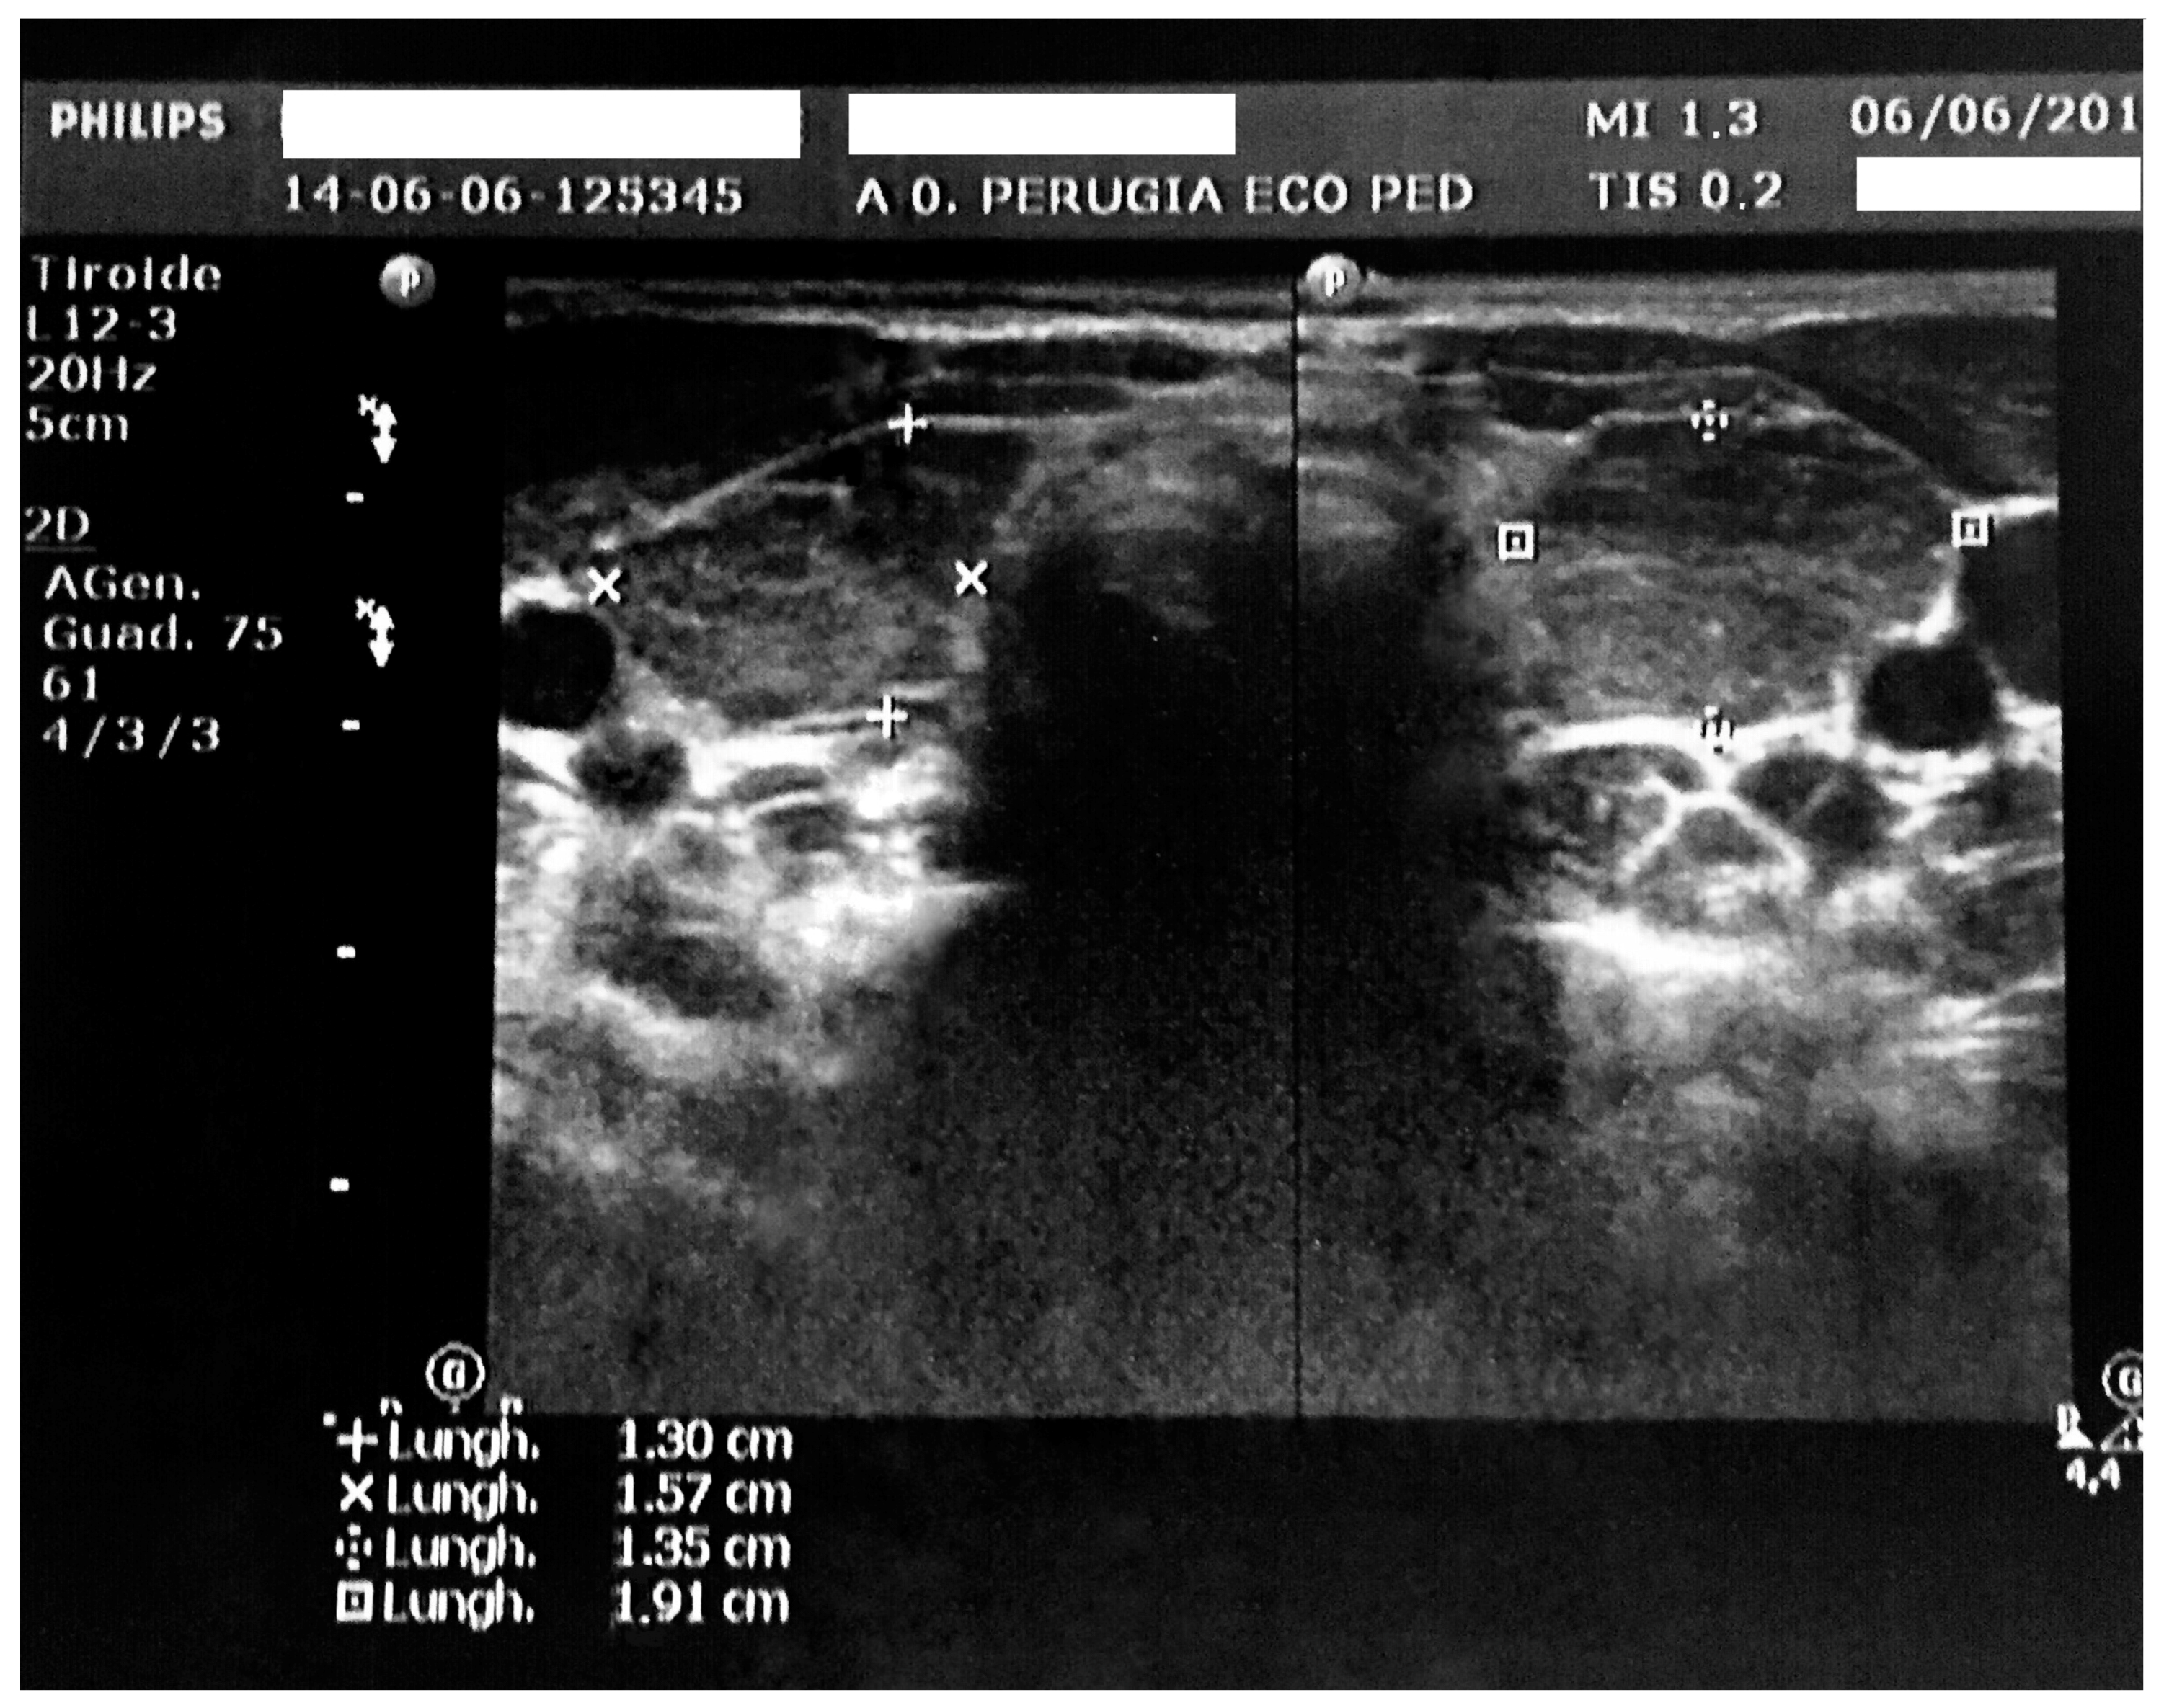

In the hospital, the clinical examination did not reveal any pathological signs other than a palpable thyroid. He had a normal heart rhythm with an innocent systolic heart murmur without pericardial rubs. The lungs were clear to auscultation and percussion bilaterally. The abdomen was soft, nontender, and nondistended. No pathologic signs were identified in the neurologic examination. Vital signs showed a pulse of 80 bpm (<2 standard deviation (SD) for age), a respiratory rate of 16 breaths/minute, SpO2 of 100% in room air, temperature of 36.5 °C, and blood pressure of 94/57 mmHg. His weight was 21 kg (78th percentile, 0.78 SD), his height was 101.8 cm (12th percentile, −1.18 SD), and his body mass index (BMI) was 20.26 (96th percentile, 1.76 SD) according to the Italian Society for Paediatric Endocrinology and Diabetes charts [11]. The mid-parental height was 166.0 cm (−1.63 SD). His bone age was delayed by one year with respect to the chronological age. On the chest radiograph, the heart had a globular appearance, and the lung fields were normal. An echocardiography confirmed and determined the effusion amount (max, 23 mm; 600 mL) with light impairment of the heart kinetics (Figure 1).

Figure 1. Echocardiography at admission, with evidence of a hyperechogenic pericardium and a large pericardial effusion.